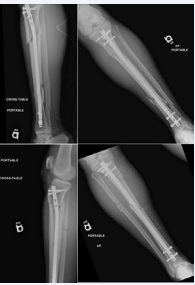

Figure 2: Anterior-Posterior and Lateral initial radiographs of a 49 year-old male who sustained bilateral segmental tibia fractures as a pedestrian stuck by a motor vehicle, which underwent placement of a Tibial intramedullary nail.